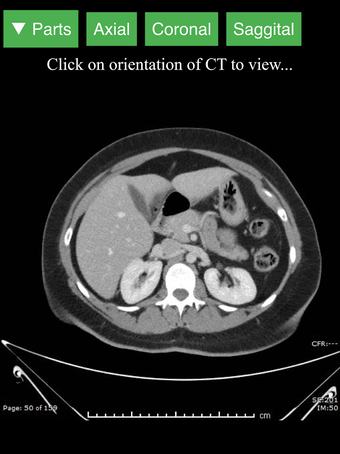

Radyoloji BT Görüntüleyicisi, doktorlar, tıp öğrencileri, radyoloji teknisyenleri ve diğer sağlık profesyonellerinin insan vücudu ve anatomisi hakkında daha fazla bilgi edinmelerine yardımcı olan faydalı bir araçtır. Uygulama, en önemli insan vücut parçalarının detaylı kesit çizimlerini içerir. Ayrıca, anatomiyi daha iyi görmek için görüntü etrafında döndürme, yakınlaştırma ve kamera hareket ettirme imkanı sunan etkileşimli bir 3D model içerir.

İnsan vücudu hakkında daha fazla bilgi edinmenize yardımcı olacak bir araç arıyorsanız, Radyoloji BT Görüntüleyicisi harika bir seçimdir. Detaylı çizimler ve etkileşimli bir 3D model içerir.